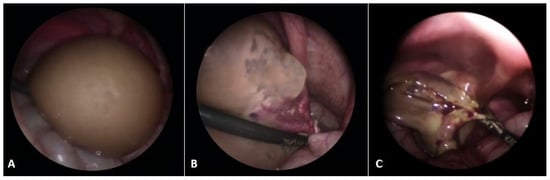

Most ovarian tumors (35–45%) in children and adolescents are derived from germ cells (e.g., mature teratomas (Figure 4), immature teratomas, yolk sac tumors (YSTs), gonadoblastomas, dysgerminomas (Figure 5), embryonal carcinoma, non-gestational choriocarcinoma, and mixed germ cell tumors), of which 80% of germ cell tumors (GCTs) are benign, while only 20% are malignant. They arise due to variations from the normal differentiation of germ cells [59,64]. Mature and immature teratomas account for approximately 80% of all ovarian GCTs and are bilateral in 5% of cases. The most common malignant ovarian GCTs in children are YSTs, while dysgerminomas are the most common malignant entity in adolescence, with bilaterality in 10% of cases. Gonadoblastoma is a rare GCT seen in girls with dysgenetic gonads [65,66].

Figure 5.

A 17-year-old female patient presented to a pediatric endocrinologist for primary amenorrhea. After diagnostic evaluation, the endocrinologist diagnosed a female phenotype and a male karyotype (46, XY). The MR scan of the abdomen showed a tumor in both gonads. The left gonad looked like a testis and the right one like an ovary. A diagnosis of a disorder of sexual development (DSD) was made. A bilateral laparoscopic adnexectomy was performed. The pathohistological examination revealed a bilateral gonadoblastoma with components of a dysgerminoma. No gonadal tissue was present in either of the removed specimens. TNM: T1bNXMX; Figo classification: 1b; (A) Intraoperative findings; (B) Macroscopic specimen after bilateral adnexectomy. Source: Archive of the Department of Pediatric Surgery, University Hospital of Split.